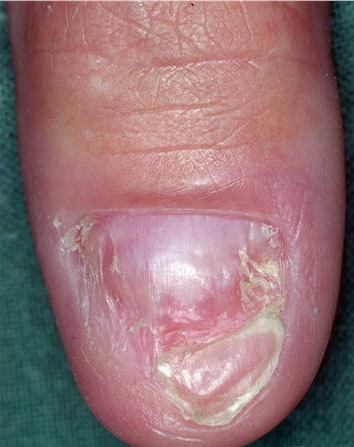

• Solitary glomus tumors have the following characteristics:

• Blue or purple

• Papules or nodules that can be blanched

• Size usually smaller than 1 cm

• Located most commonly in acral areas, especially subungual areas of fingers and toes